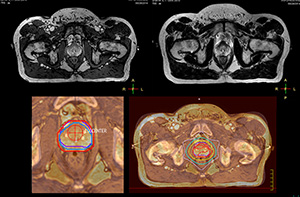

Beaumont Health System brought MRI into its radiation therapy routine practice by implementing the comprehensive Ingenia 3.0T MR-RT Oncology Configuration.

“The main reason to integrate MR imaging in RT planning is the superb soft tissue contrast that allows detailed delineation of tumors and healthy organs, which is crucial for RT planning,” says Craig W. Stevens MD, PhD.

“The good visualization is why a lot of cancer treatments can benefit from MR based treatment planning, because if we can localize a tumor better, we can aim the radiation beam at it better. This potentially allows us to shrink our margins and spare more healthy tissue.”

“Using MR, the prostate is well delineated. We quickly see the edges of cancerous tumors like in prostate cancer, and as normal structures can be defined, we can optimize the treatment plan to protect these organs and their normal function. This can potentially improve the outcome. And it improves workflow as well. We can contour more quickly, confident that the tumor is going to be in the field.”

“When a patient registers, first CT simulation and MR simulation are done, followed by CT-MR registration on Pinnacle3. Then the target and normal organ delineation is performed on MR images. Meanwhile we create a reference CT image for online treatment and localization correction. During the treatment phase we can perform additional MRI scans to visualize the anatomy changes and create an adaptive plan. This plan basically adapts the treatment plan to the changes.”